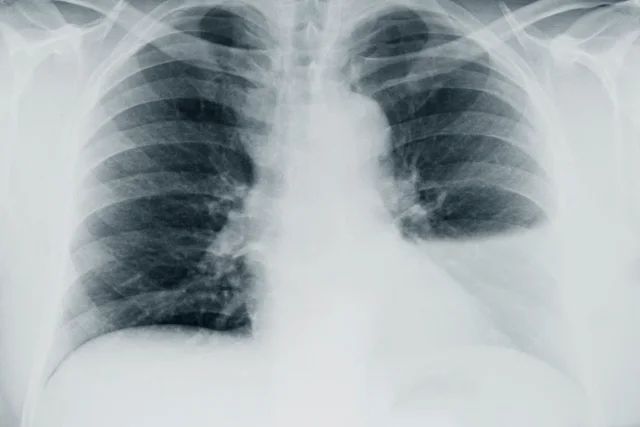

Datos de imagen

Los estudios de imagen útiles en la evaluación de los pacientes con derrame pleural consisten en:

En pacientes con sospecha clínica de derrame pleural se recomienda realizar inicialmente radiografía de tórax (Postero-Anterior y lateral).

- La sensibilidad de la radiografía de tórax para detectar derrame pleural es 24-100% con especificidad 85-100%

- En casos de derrame pleural mínimo, se solicita una radiografía en posición de decúbito lateral del lado afectado.

- En una radiografía de tórax

- 50 a 75 ml de líquido pleural producen borramiento del ángulo costodiafragmático posterior en la radiografía lateral, (“signo del menisco”).

- 200 ml de líquido pleural producen borramiento de los ángulos cardiofrénico y costodiafragmático.

- La radiografía de tórax lateral puede ayudar a confirmar la presencia de líquido pleural que no se observa en la radiografía postero

anterior. - Los derrames pleurales pequeños pueden detectarse en una radiografía en posición decúbito lateral sobre el lado afectado

Los derrames loculados ocurren con más frecuencia en asociación con condiciones que causan intensa inflamación pleural como el empiema, el hemotórax o la tuberculosis.

- Los derrames pleurales masivos llegan a ocupar todo el hemitórax afectado y desplazan el mediastino hacia el lado opuesto.